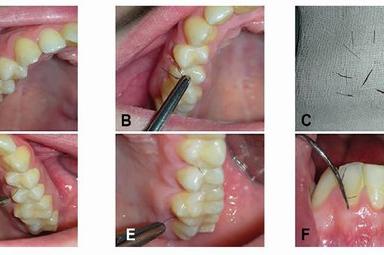

У молодой итальянки выросли волосы на деснах. Фото

К врачам из университета «Луиджи Ванвителли» обратилась 19-летняя итальянка с жалобой на волосы, которые активно росли в ее ротовой полости. Такое явление известно в медицине как гирсутизм десен. Ранее подобные случаи уже были зафиксированы, но исключительно у мужчин.

При осмотре у пациентки были обнаружены волоски похожие на ресницы, которые росли прямо из десны между верхними зубами. Правда, ткань, из которой росли волосы, была необычно утолщена.